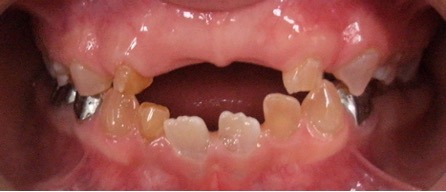

El examen clínico intraoral reveló alteración de la estructura y color de las piezas primarias, atrición y pérdida de la dimensión vertical (Figura 2). Radiográficamente se observó la presencia de coronas con marcada constricción cervical y raíces cortas (Figura 3). Presentaba alto riesgo cariogénico, por la presencia de lesiones de caries activas y dos restos radiculares, sumado a la anomalía estructural de la dentina (riesgo biológico específico) y bajo riesgo gingivoperiodontal. El riesgo socio-económico era alto por provenir de una familia con marcadas limitaciones económicas. Luego de la anamnesis, examen clínico y radiográfico, e interconsulta con el médico de cabecera se estableció el diagnóstico de DI Tipo I asociado a OI tipo I. Se planificó un tratamiento integral y preventivo con los objetivos de devolver forma y función, y proteger y evitar el desgaste de los tejidos conductas que pudieran interferir con el tratamiento.

Figura 2: Examen clínico intraoral del maxilar superior e inferior y vista anterior. Año 2007